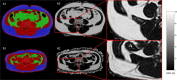

Cachexia, a multifactorial wasting syndrome, is highly prevalent among advanced-stage cancer patients. Unlike weight loss in healthy humans, the progressive loss of body weight in cancer cachexia primarily implicates lean body mass, caused by an aberrant metabolism and systemic inflammation. This may lead to disease aggravation, poorer quality of life, and increased mortality. Timely detection is, therefore, crucial, as is the careful monitoring of cancer progression, in an effort to improve management, facilitate individual treatment and minimize disease complications. A detailed analysis of body composition and tissue changes using imaging modalities-that is, computed tomography, magnetic resonance imaging, (18F) fluoro-2-deoxy-D-glucose (18FDG) PET and dual-energy X-ray absorptiometry-shows great premise for charting the course of cachexia. Quantitative and qualitative changes to adipose tissue, organs, and muscle compartments, particularly of the trunk and extremities, could present important biomarkers for phenotyping cachexia and determining its onset in patients. In this review, we present and compare the imaging techniques that have been used in the setting of cancer cachexia. Their individual limitations, drawbacks in the face of clinical routine care, and relevance in oncology are also discussed.